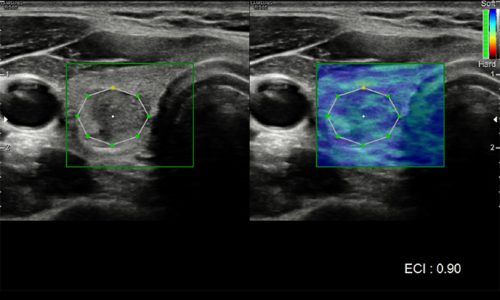

L’ecografia è una metodica diagnostica non invasiva che utilizza ultrasuoni (onde sonore) emessi da speciali sonde appoggiate sulla pelle del paziente. Questo permette di visualizzare organi, ghiandole, vasi sanguigni, strutture sottocutanee e persino tessuti muscolari e tendinei in diverse parti del corpo.

Il nostro Centro dispone di un sistema ad ultrasuoni Samsung, esattamente l’Ecografo Samsung V8, strumentazione estremamente versatile, che consente di offrire una straordinaria qualità d’immagine e funzionalità diagnostiche avanzate per lo studio dei diversi distretti corporei.